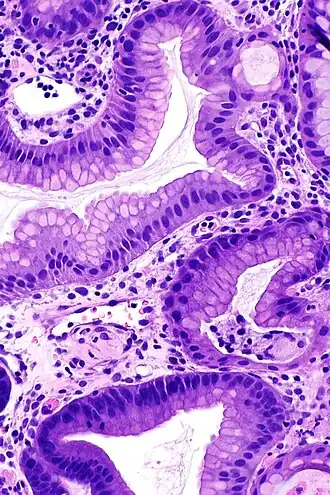

Bij het syndroom van Ménétrier wordt de maag gekenmerkt door grote, kronkelige maagplooien in de koepel van de maag (fundus gastricus) en het lichaam, waarbij het antrum (middelste deel van de maag) over het algemeen gespaard blijft, waardoor het slijmvlies een kasseien- of cerebriform (hersenachtig) uiterlijk krijgt.[4] Histologisch gezien is het meest karakteristieke kenmerk massieve foveolaire hyperplasie (hyperplasie van oppervlakte- en klierslijmcellen).[5] De klieren zijn langwerpig met een kurkentrekkerachtig uiterlijk en cystische verwijding komt vaak voor. De ontsteking is meestal slechts bescheiden, hoewel sommige gevallen duidelijke intra-epitheliale lymfocytose vertonen. Diffuse of vlekkerige klieratrofie, duidelijk als hypoplasie van pariëtale (exocrinocyti parietales) en hoofdcellen (exocrinocyti principales), is typisch.[3]